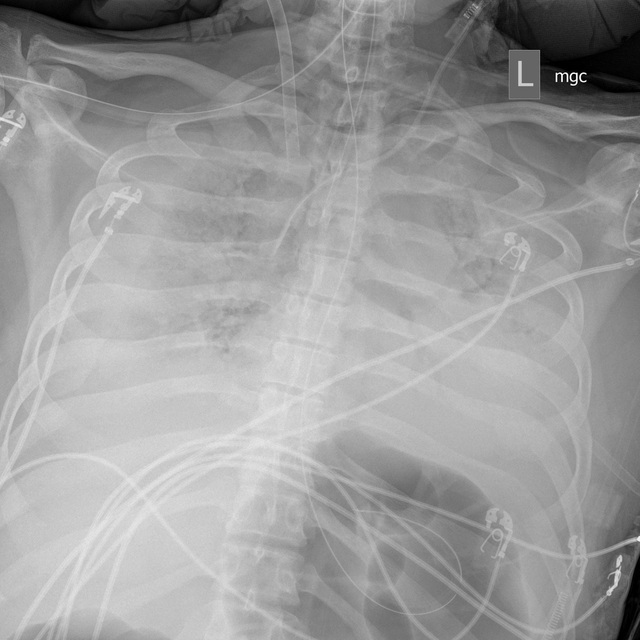

Lúc này, phổi của Jim cứng đến mức chỉ số đo độ đàn hồi của phổi của ông chỉ dưới 10, trong khi chỉ số này thường trên 100 với người khỏe mạnh và khoảng 30 ở những người bị suy hô hấp nặng.

Hình ảnh X-quang phổi của Jim ngày 27/3 tràn ngập màu trắng. Các bác sĩ cho biết đây là một trong những hình ảnh X-quang phổi tệ nhất họ từng thấy. (Ảnh: NYT)